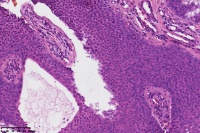

汗孔瘤?

性别

女

年龄

50岁

足底丘疹

汗孔瘤。